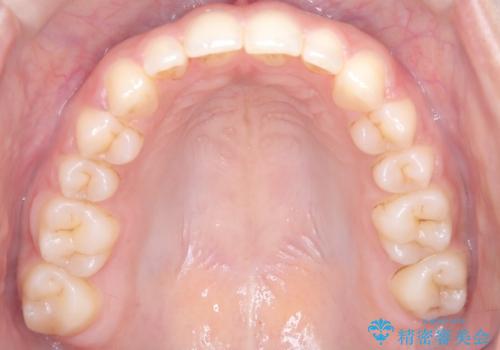

- 患者様は、前歯が出ている状態(上顎前突)と隙間を閉じたいというご希望で来院されました。診断の結果、骨格性の上顎前突が確認されたため、理想的には外科矯正が必要であることを説明しましたが、患者様の「非抜歯でできる範囲で治療を進めたい」という希望を尊重し、矯正治療計画を立てました。治療目標は、前歯の突出を可能な限り改善し、隙間を閉じることに重点を置きました。

本症例では、非抜歯での治療を選択したため、スペースを確保するためにIPR(歯間削合)を行い、歯列を整えました。オーバージェット(上の前歯と下の前歯の水平的なズレ)は残る結果となりましたが、見た目や機能の改善を重視し、患者様と治療計画を共有しながら進めました。治療中は、歯列全体のバランスと噛み合わせを考慮しつつ、矯正装置の適切な使用を徹底しました。当初の計画通りに治療を完了し、患者様にも満足していただけました。